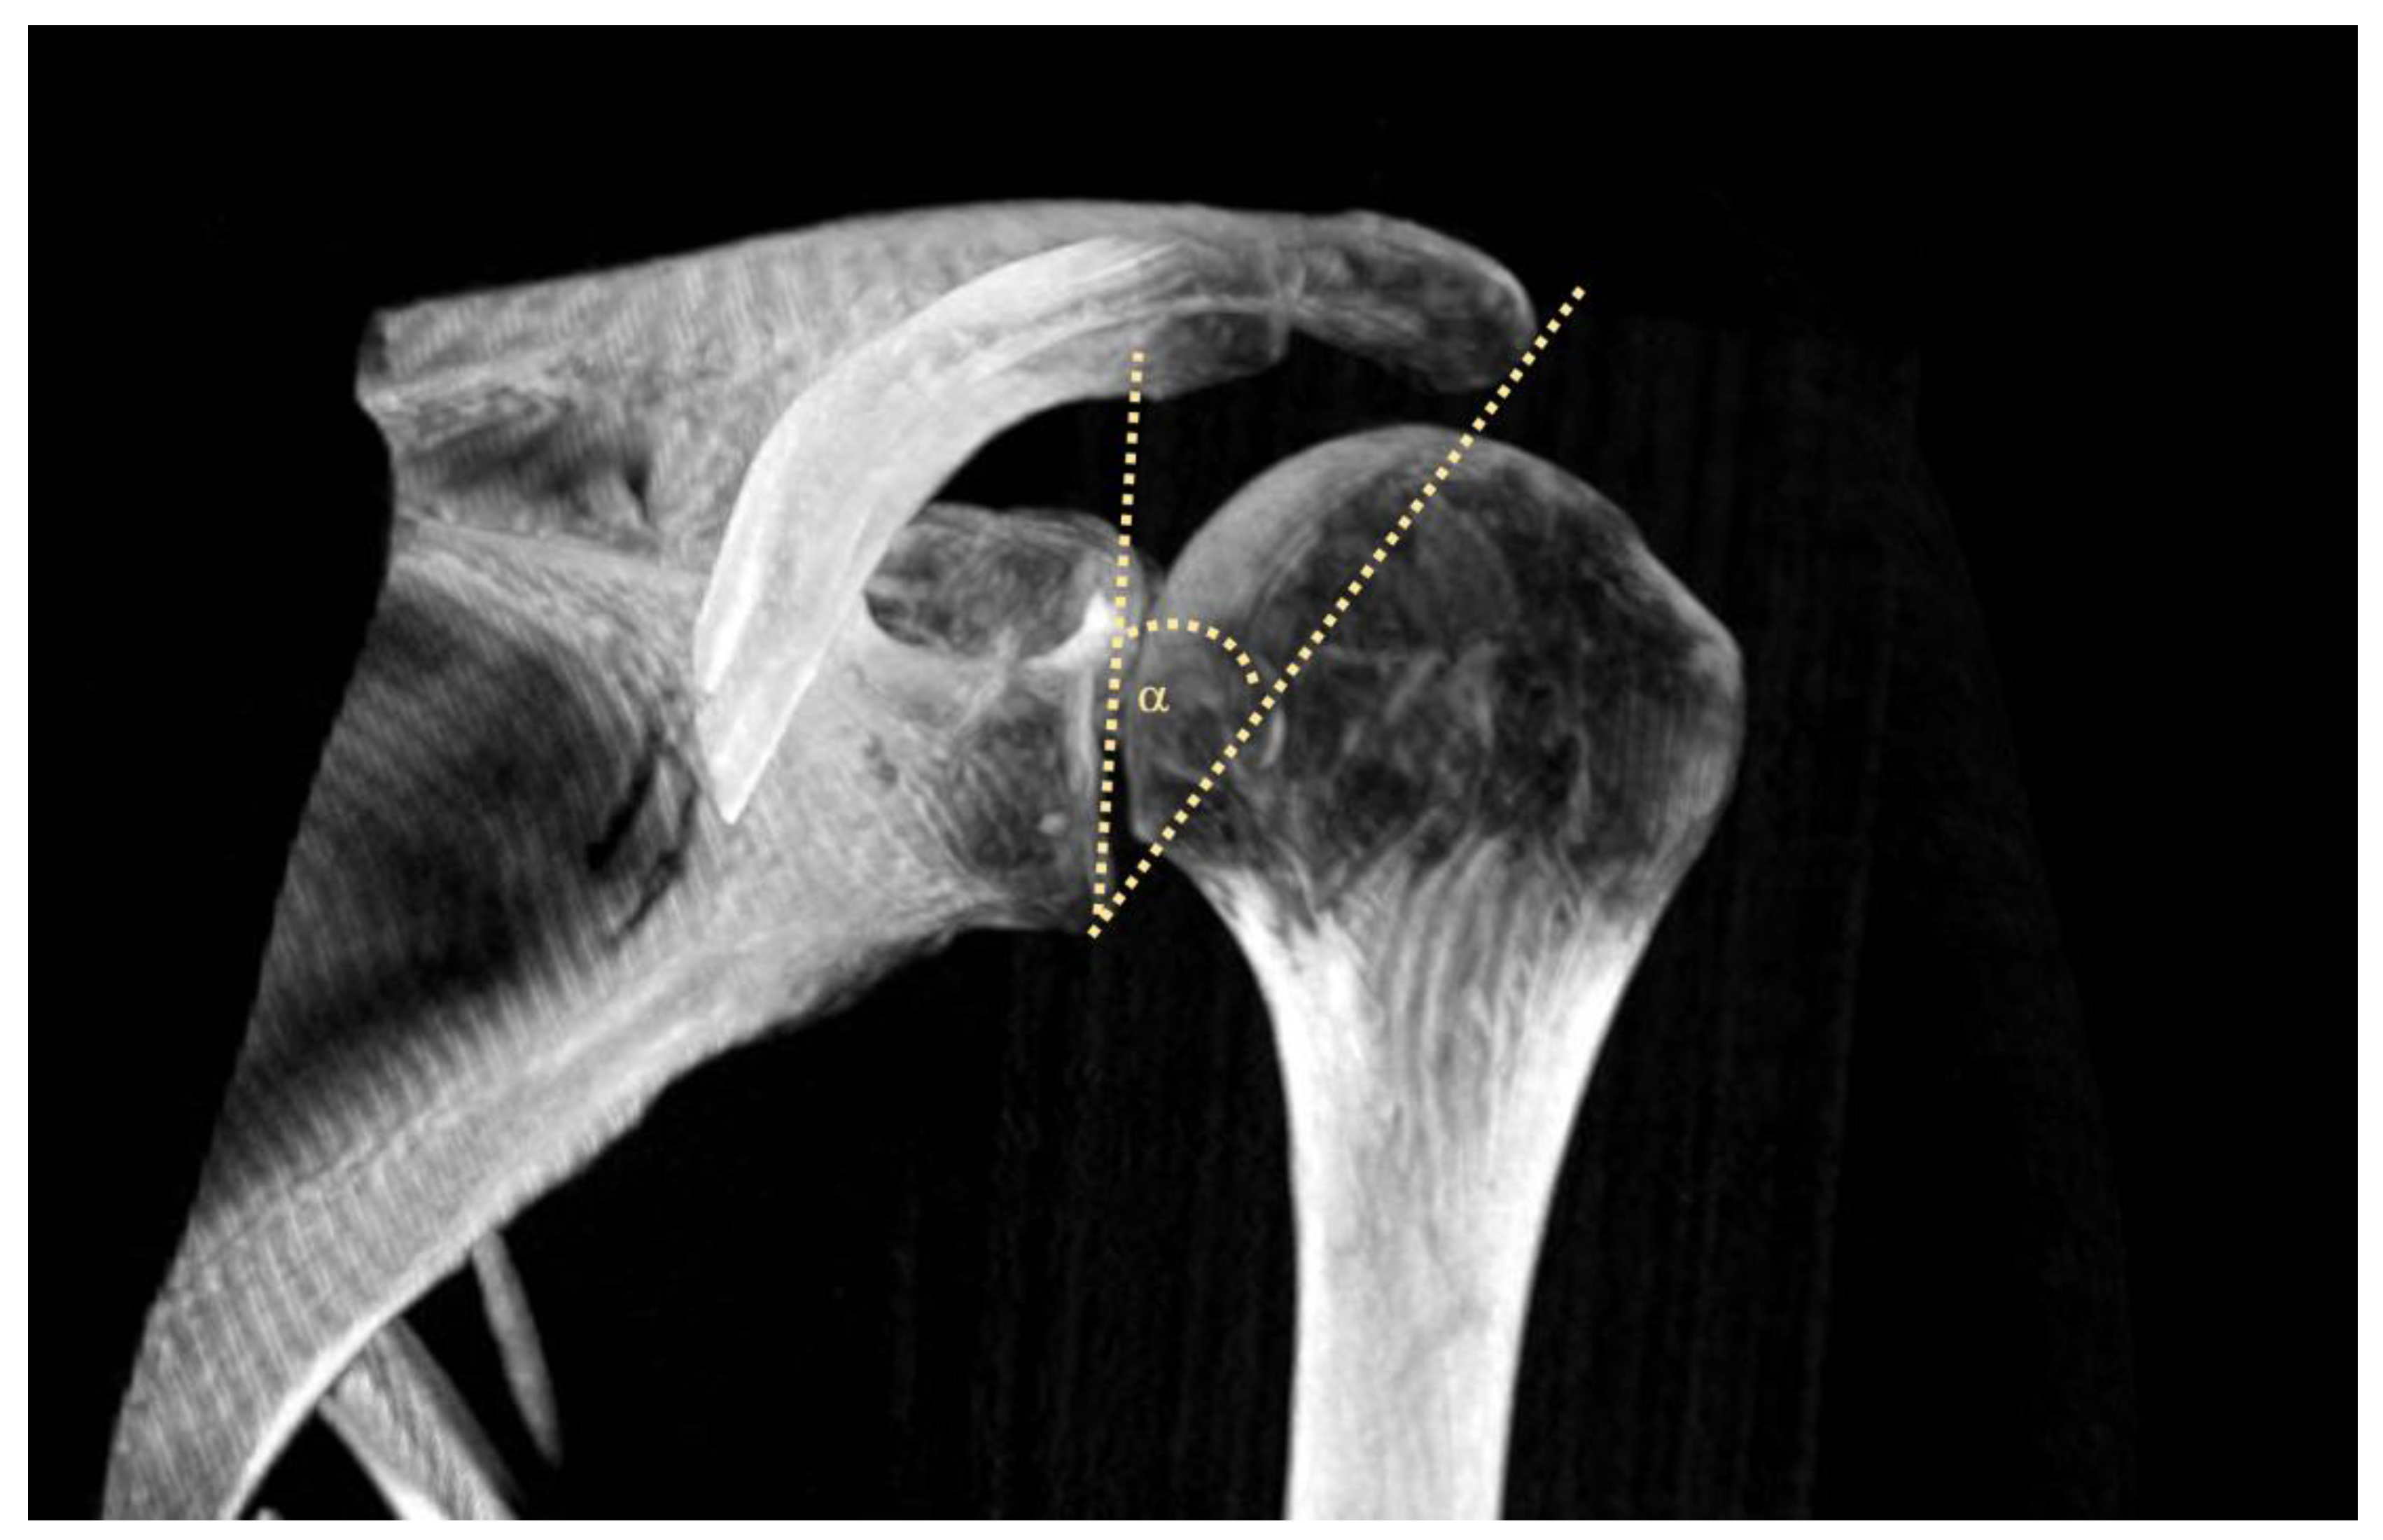

2.4. MRI-Assisted Assessment of the CSA